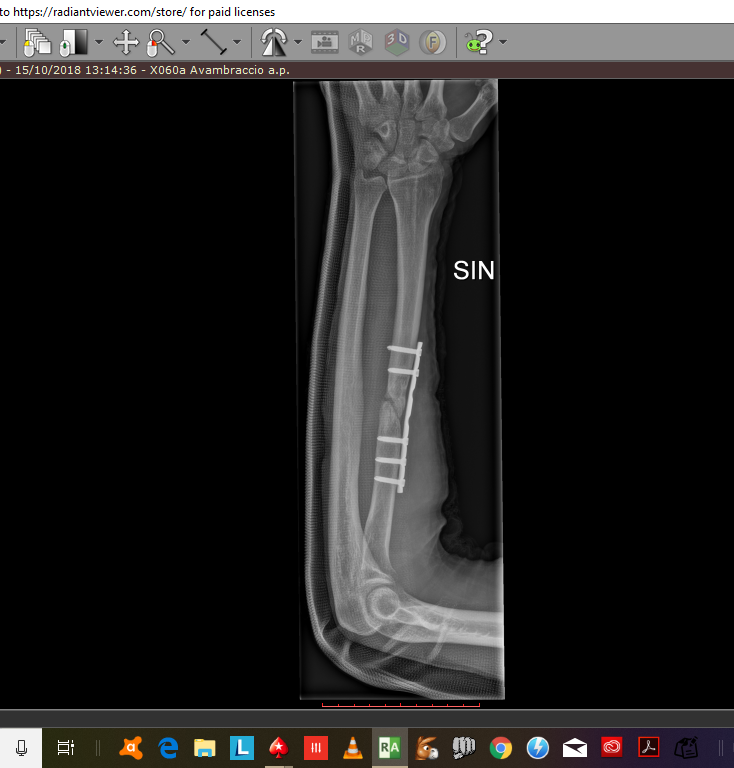

4/06/2018 - viene eseguito l' intervento ed ingessato il braccio . Viene rimossa la terza vite , quella che nella prima radiografia è molto vicina alla frattura ,anzi quasi dentro la frattura . Come potete notare nell rx di ottobre difatti la vite manca.

10/01/2019 - Ad oggi sono ancora ingesato e la frattura mooolto lentamente sembra guarire . considerando che sono passati già quasi 8 mesi dall'intervento ( sono ingessato da 8 mesi ) ed eseguo visita ed rx ogni mese circa , credo che dovrò rioperarmi .

2 Considerando che la terza vite ( a partire da sopra per intenderci ) che si vede nella prima rx è stata rimossa nell'ultimo intervento , allego anche l'rx fatta dopo quest'ultimo intervento, secondo voi potrebbe essere a causa di quella vite messa malissimo , quasi nella frattura in pratica , il mancato consolidamento del primo intervento ?

una delle viti che hanno messo nel primo intervento fatto in clinica è messa praticamenet nella frattura e per quello non è guarita con il primo intervento .